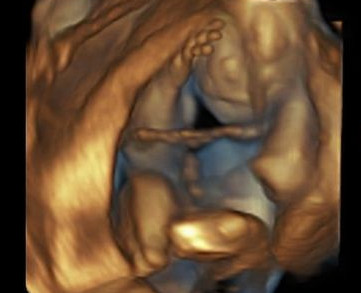

5D/HD is the latest in technology advancements when it comes to three dimensional imaging. It often provides a very real life like image that is pink/flesh toned.

Below are 5D/HD Images